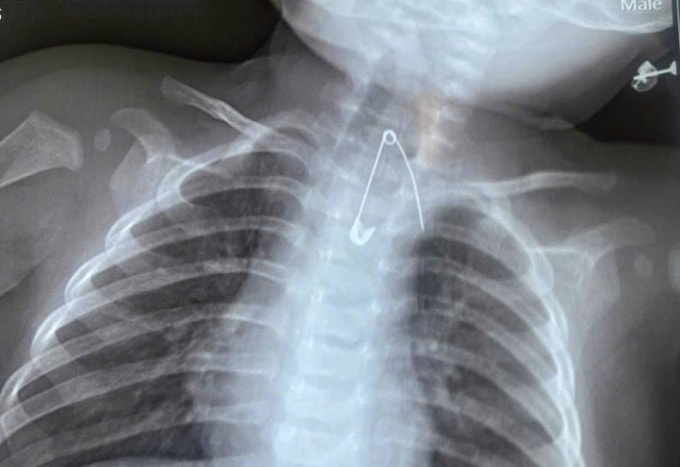

Chiếc kim băng găm vào thực quản bé 7 tháng tuổi

Bé trai 7 tháng tuổi sốt, ho kéo dài hai ngày, bác sĩ phát hiện chiếc kim băng mắc ở thực quản bé, sát động mạch chủ.

Các bác sĩ chụp chiếu phát hiện chiếc kim nằm trong mô mềm tại 1/3 trên thực quản, sát động mạch chủ. Dị vật tiềm ẩn nguy cơ gây tổn thương mạch máu lớn, xuất huyết ồ ạt và đe dọa tính mạng nếu không được xử trí kịp thời.